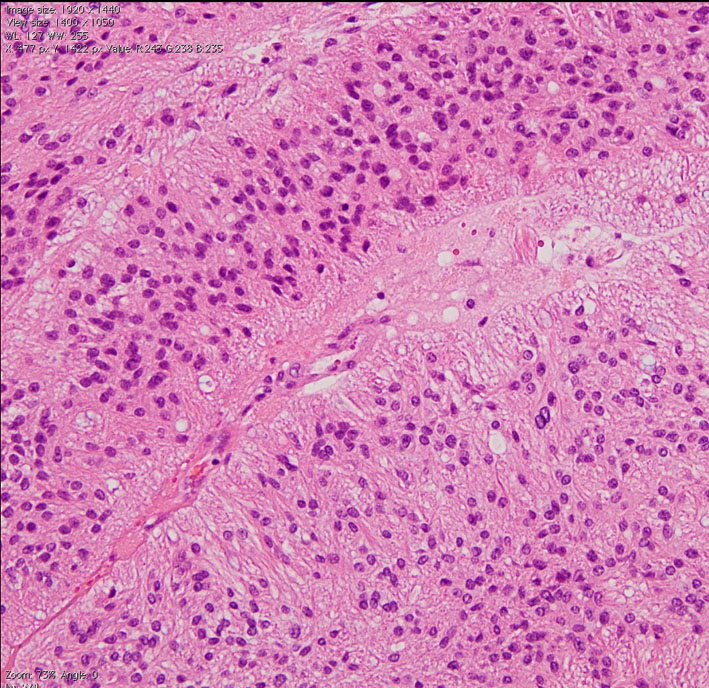

第4脳室床に発生した典型的な上衣腫 EPN-PFA の画像です。水頭症になって,頭痛と嘔吐,意識障害で発症しました。典型的なMRI画像と病理所見です。MRIでは第4脳室からマジャンディー孔を越えて脊髄背側まで長く腫瘍が伸びています。腫瘍内部に小さなのう胞が複数みられます。病理像では,血管周囲に細胞核がない無核野が認められます。血管周囲に伸びた繊細な単極性突起が集まった領域です。これは,血管周囲偽ロゼット perivascular pseudorosette という上衣腫に特徴的な病理所見です。

摘出した標本のHE染色です。左側ではperivascular pseudorosette(血管周囲の無核野)がみられ,右側ではependymal tube (ependymal canal) が認められます。

グレード2の組織像です。血管周囲に無核野があり,腫瘍の核は血管から離れているパターンが特長です。perivascular pseudo-rosetteといいます。